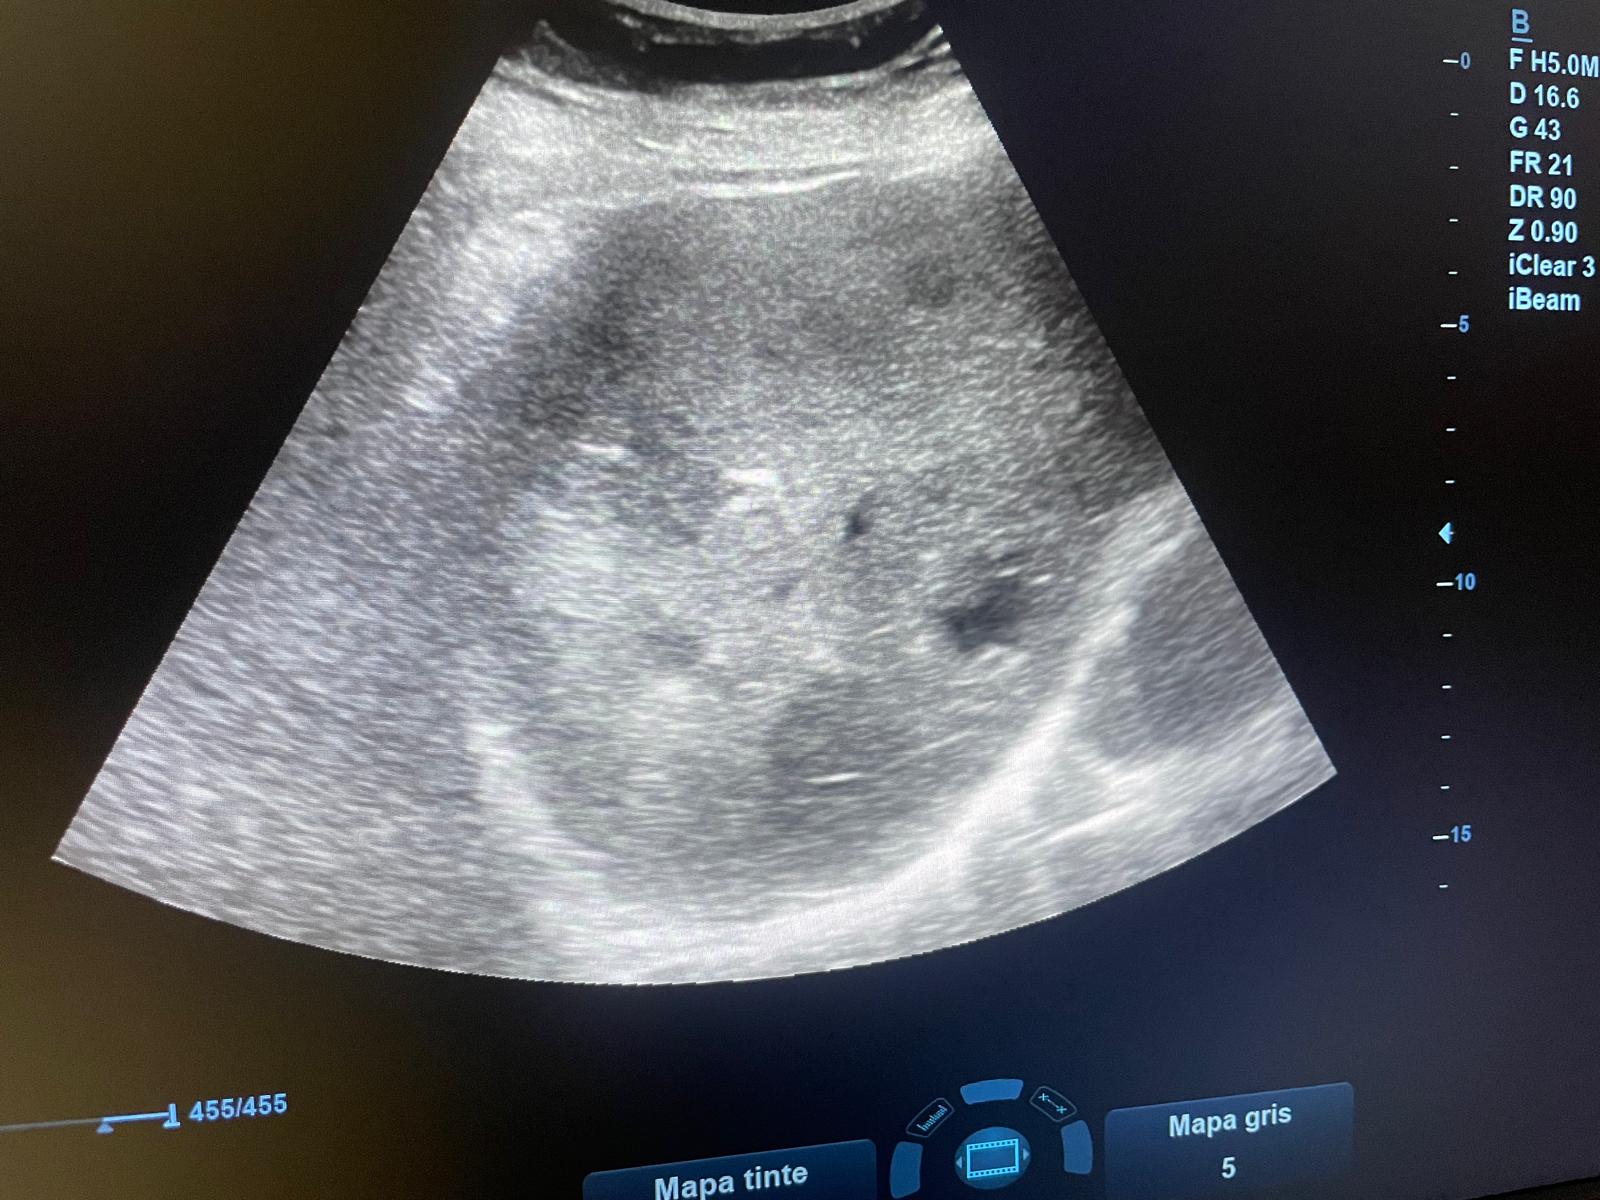

Paciente mujer de 96 años con antecedentes de HTA, DLP, DM tipo 2, cardiopatía isquémica que acude a consulta por cuadro de distensión abdominal, astenia, anorexia y hábito estreñido de dos semanas de evolución.Hallazgos ecográficos

Se realiza ecografía abdominal en la que se objetivan numerosas loes hepáticas heterogéneas algunas en ojo de buey sobre todo en cúpula hepática, sugerentes de metástasis hepáticas.Pruebas complementarias